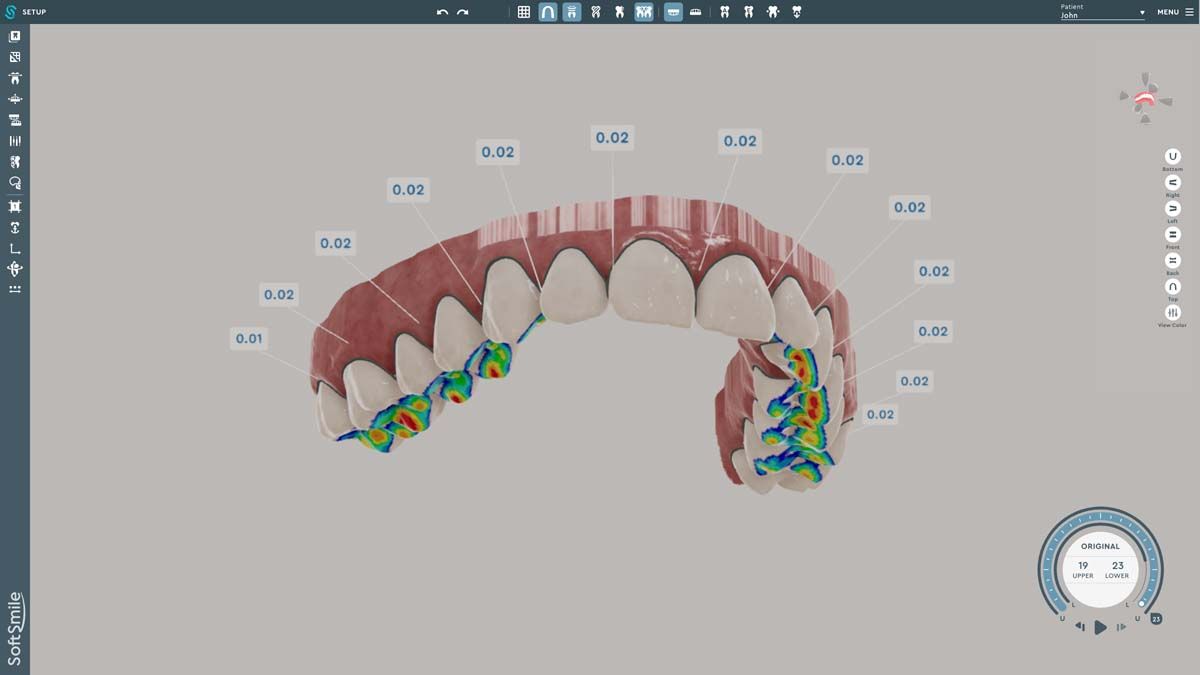

We used to try showing patients their clinical situation on 2D x-rays and demonstrating treatment using models. Later, digital intraoral cameras helped, but they could not show much more than what a patient could see in a mirror. Today, it is possible to show patients every angle of their clinical situation in hyperrealistic 3D with a CBCT scan. Now, when I recommend treatment to patients and they ask why, I am armed with an interactive image captured by my CS 8200 3D extraoral imaging system (Carestream Dental). I scroll through the tooth and bone, point out lesions below the surface, and show why there is or is not enough bone for an implant. If you use something like the Prosthetic-Driven Implant Planning module to automatically merge an intraoral scanner file with the CBCT scan, you create an even more accurate picture. How much easier is it for the patient to accept treatment when they are seeing the end results of that treatment?